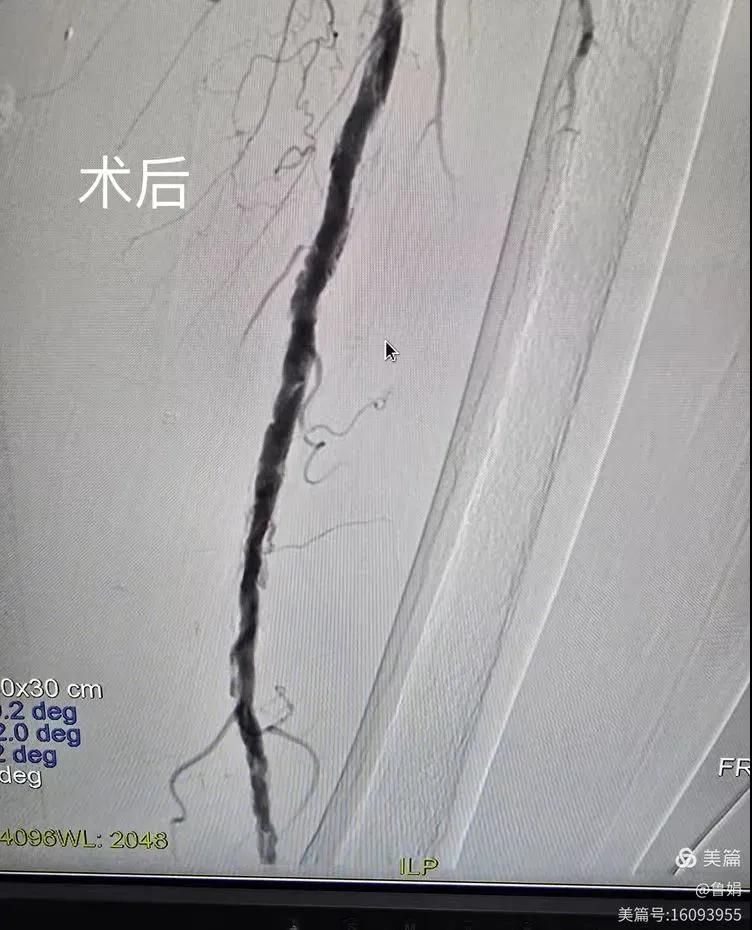

據(jù)悉,該患者,女,73歲,下肢動脈硬化閉塞癥,“以靜息痛,間歇性跛行”入院,CTA評估:股淺動脈,腘動脈間斷性多段重度狹窄,外二科血管外科團隊根據(jù)患者病情,結合檢查結果,經過科室會診后,決定對該病人行介入治療。手術由周創(chuàng)業(yè)副主任與北大一院血管外科專家郭宏杰教授聯(lián)合開展,對股淺動脈,腘動脈重度閉塞段行血管開通+藥涂球囊擴張成形,術后狹窄明顯緩解,血流恢復!